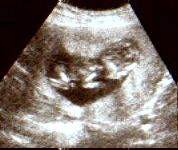

Unser Nachwuchs. 3800 gr. und 55 cm.

Geburtstag ist der 07.09.2007 um 12:00 Uhr.

Er ist per Kaiserschnitt gekommen.